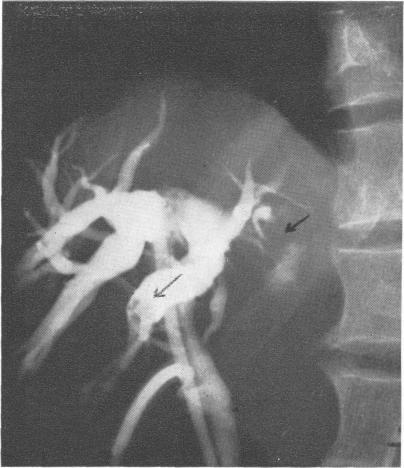

Hepatic calculi.